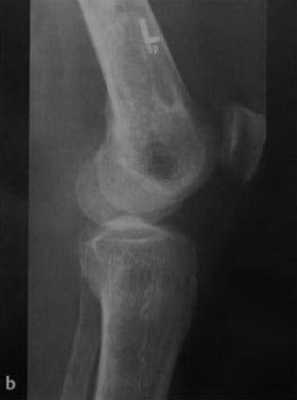

а, b Инфаркт зрелого костного мозга. (а) Сагиттальная протонная плотно-взвешенная МРТ с подавлением МР-сигнала от жировой ткани. Изображение демонстрирует гирляндовидный склеротический край и центральный участок с сигналом жирового костного мозга. Множественные некротические зоны расположены преимущественно в метадиафизальной области, однако несколько находятся непосредственно рядом с суставом, в связи с чем имеется риск уплощения суставных поверхностей;

![Снимки МРТ и КТ. Инфаркт кости]()

b) Рентгенологическое исследование демонстрирует выраженный склеротический край и центральный участок снижения рентгенопрозрачности в дистальном отделе бедренной кости и в большеберцовой кости. Проксимальный отдел бедренной кости демонстрирует участок частичного грубого склероза, который иногда трудно отличить от энхондромы.